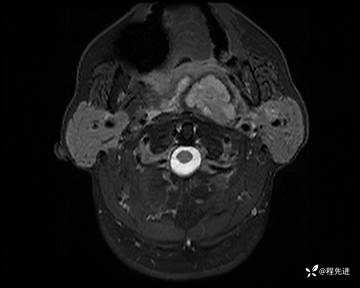

MRI平扫+增强:

T1:

T1增强: